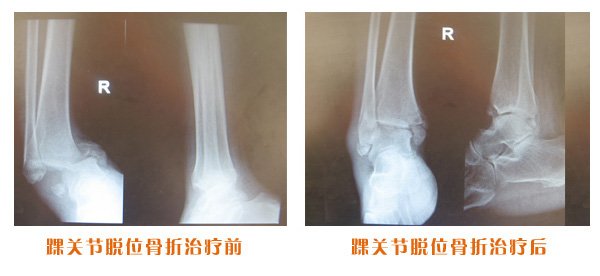

肥城市安駕莊梁氏骨科醫(yī)院是一所以梁氏手法正骨配合膏藥為特色的現(xiàn)代化專科醫(yī)院。